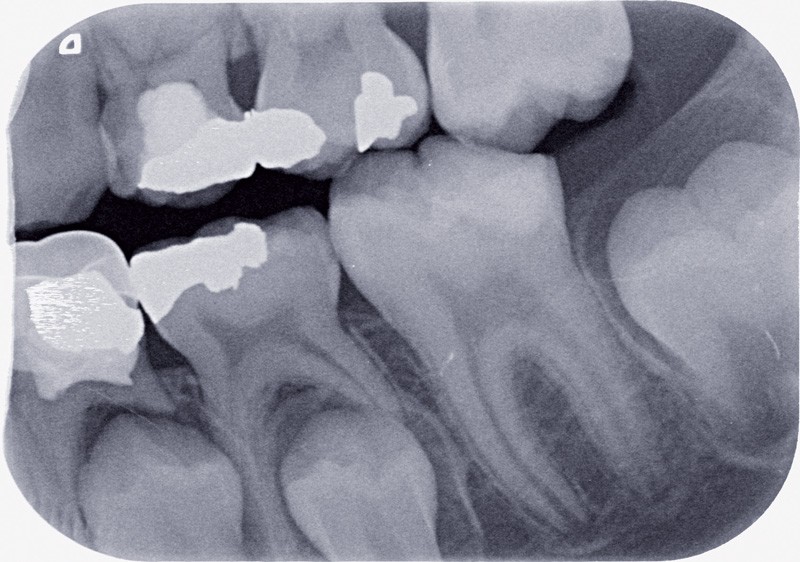

La période d’immaturité dentaire, bien que très brève au regard de la durée de vie de la dent sur arcade, apparaît comme déterminante pour sa pérennité future. Cette phase de quelques années entre l’émergence dans la cavité buccale et la mise en place de la jonction cémento-dentinaire apicale, est essentielle pour que la dent acquière sa maturité tissulaire.

Dans l’approche médicale contemporaine de la dentisterie, le respect des dents permanentes est un impératif et toutes les stratégies préventives et thérapeutiques doivent être mises en œuvre dans ce sens, et ce, à plus forte raison, lorsqu’elles sont jeunes et immatures. C’est pourquoi, la dent immature, indemne de pathologie, doit être au centre des stratégies de prévention primaire, c’est-à-dire l’ensemble des mesures qui visent à éviter le développement de lésions carieuses. Elle doit également faire l’objet des méthodes de prévention secondaire, c’est-à-dire d’interception des lésions initiales. Face à la pathologie carieuse ou traumatique, l’immaturité de structure oblige à reconsidérer les thérapeutiques conservatrices en fonction du stade de formation radiculaire et apicale. Les traitements portent en effet sur des structures en évolution et doivent donc permettre aux structures dentaires et alvéolaires de parachever leur édification. Si l’immaturité des tissus constitutifs de la dent la rend plus vulnérable face à la maladie carieuse, cette même immaturité rend possible des thérapeutiques de prévention et de régénération en dentisterie conservatrice et en traumatologie, thérapeutiques qui ne seront plus efficientes une fois la dent mature.

Immaturité amélaire

La période d’éruption de la dent, c’est-à-dire le laps de temps entre l’apparition des pointes cuspidiennes dans la cavité buccale et son occlusion fonctionnelle, est conséquente. Elle est par exemple de 15 mois en moyenne pour la première molaire et 27 mois pour…